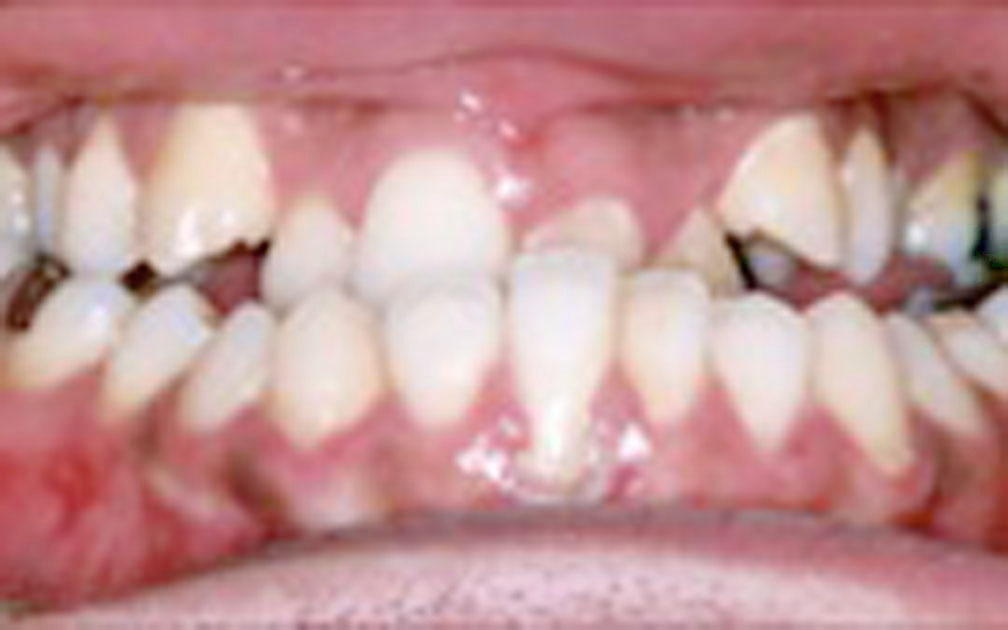

矯正の症例4 (診断名)開咬(カイコウ)

(患者様の主訴)前歯で噛めない

(治療開始年齢)15歳9カ月

(主な治療装置)エッジワイズアプライアンス

(抜歯部位)上下第1小臼歯4本抜歯

(治療期間)2年5カ月

(治療費)¥860000

(個別リスク・副作用)当初より前歯部歯根が短く、前歯部の挺出が必要な症例なので、さらに歯根が短くなるリスクがある。

舌の突出の影響が大きいため、矯正治療後も舌癖により後戻りが起こるリスクがある。長期にわたる舌癖のコントロールが必要となる